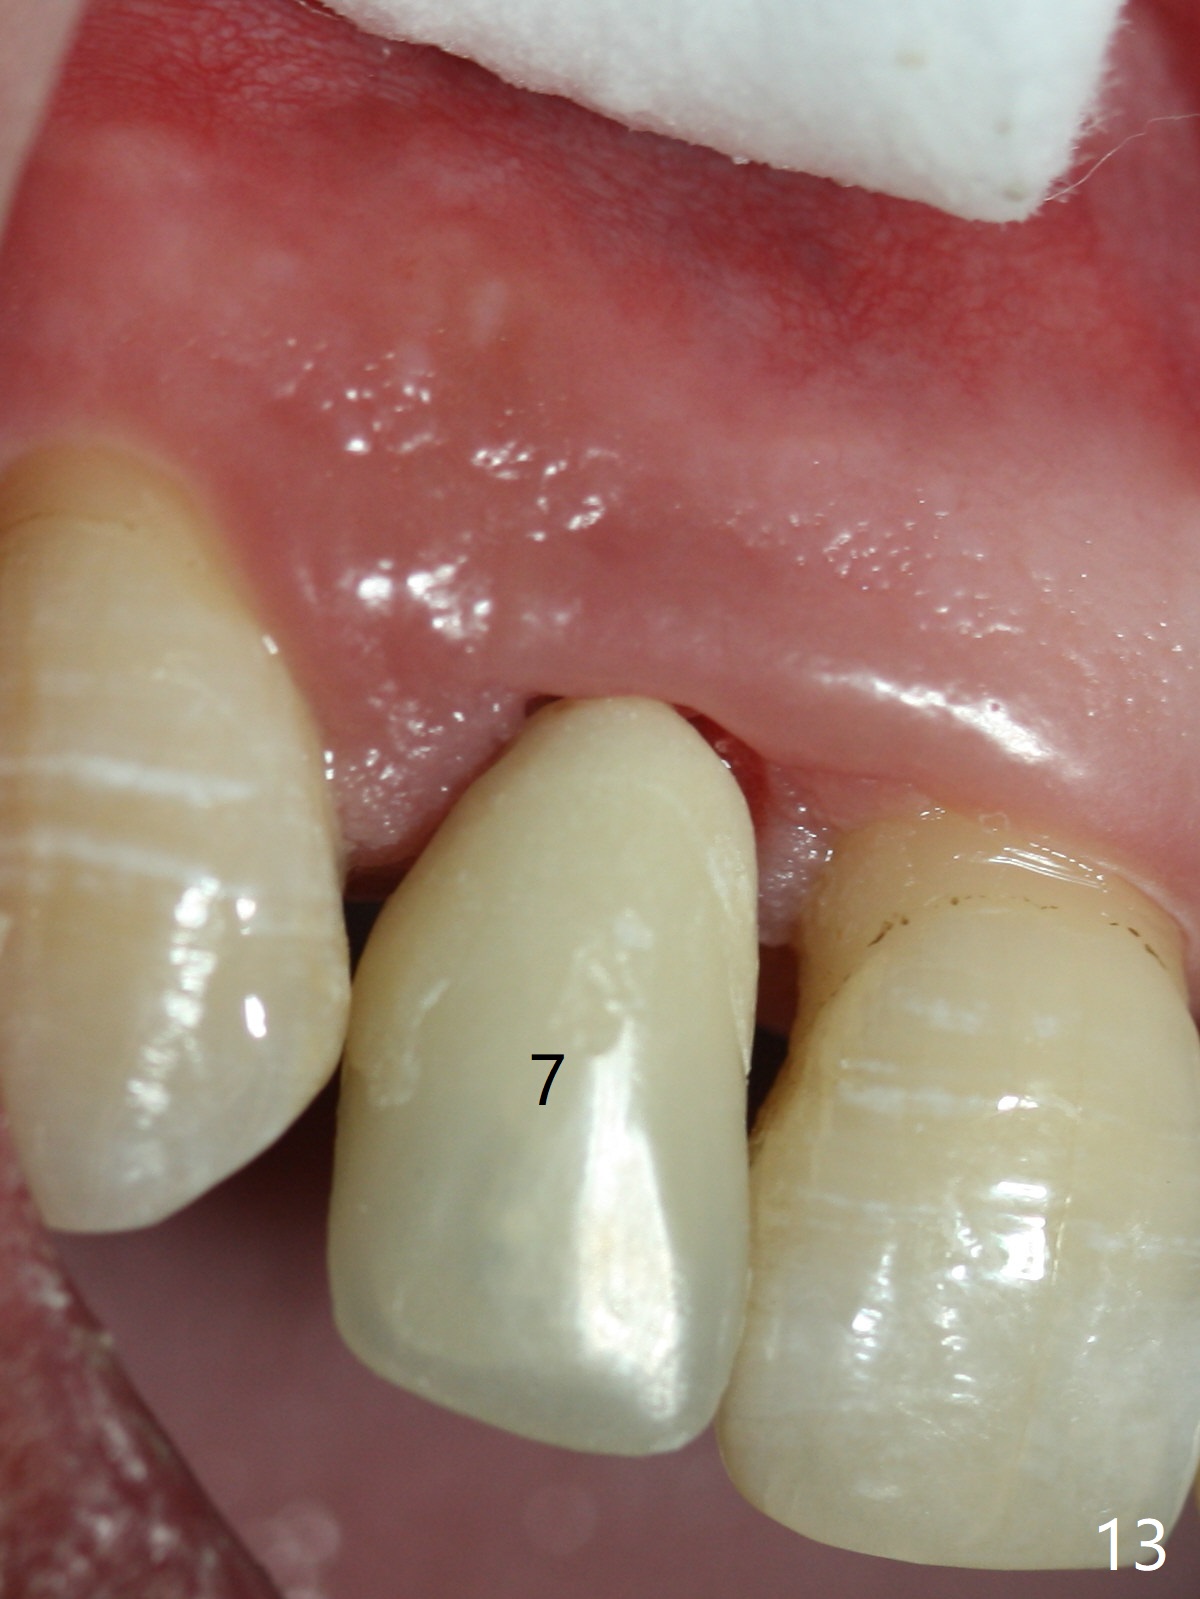

The tooth #7 has receded gingiva preop (Fig.1). The gingiva appears to have regenerated with a provisional (margin just modified) 6 months postop (Fig.13).